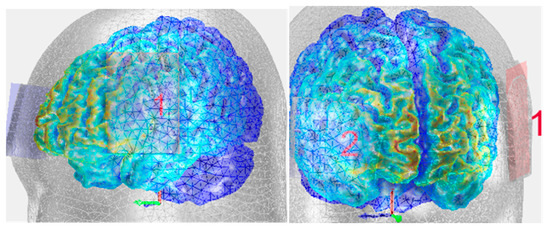

In the second part of the program, the procedures were similar, with the exception that the exercises and the stimulation were performed at LA’s home with occasional clinical contact (once per round) and the overall support of his partner. LA received anodal tDCS stimulation over the left IFG paired with language therapy, and tDCS was administered with the DC-Stimulator Plus®, NeuroConn. Two relatively small anodes and cathodes (5 × 5 cm2) were used to increase focality [31]. The electrodes were inserted in saline-soaked sponges (0.17 mL/cm2) before being positioned. The anode was placed over the left Broca Area (F7), individually located with the Beam A8 system [32]. The cathode was positioned over the right inferior frontolateral gyrus [23] (AF8). We decided to place the returning electrode (cathode) around AF8 in order to have a better control of the electric current flow over the surface of the left inferior frontal gyrus (Figure 2). In addition, the tDCS from NeuroConn is designed to place electrodes on brain and not on the shoulder because of the length of cable [33]. A standard 1.5 mA stimulation was first planned, but during the pilot trial, the patient asked to decrease the intensity. Thus, 1 mA intensity was chosen in order to compromise between the literature and the patient’s feelings [17]. The current was ramped up for 30 s at the beginning and ramped down for 15 s at the end of the stimulation.

Figure 2.

The current distribution in the brain with the anode (1) placed over the left Broca Area (F7) and the cathode (2) placed over the right inferior frontolateral gyrus (AF8).